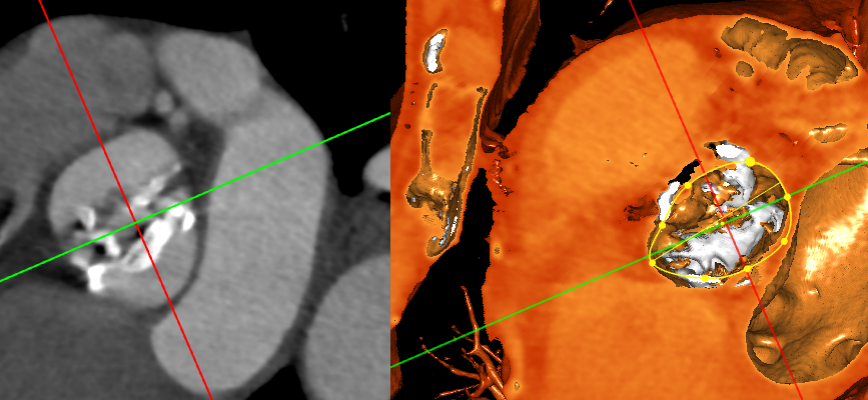

术前心胸外科、心血管内科、超声科、麻醉科、体外循环、介入室等科室进行了术前讨论和术前策略分析:该患者主动脉瓣属于钙化狭窄的Type0型二叶瓣,左右冠脉同窦,无冠窦可见团状钙化,左右同窦钙化相对较少,主动脉瓣环周长82.2mm、呈现椭圆形,左室流出道周长89.6mm,主动脉窦宽28.7mm/33.7mm/34.9mm、窦宽可,STJ周长93.5mm、高度22.2mm,升主动脉周长111.7mm。患者心室壁明显增厚心尖较薄。左冠高度15.4mm右冠高度14.9mm,双冠高度可。患者右股动脉分叉点位于股骨头下缘,穿刺点内径为8.1mm,血管无明显钙化轻度迂曲。左股动脉分叉点位于股骨头下缘,穿刺点内径为7.8mm,血管无明显钙化轻度迂曲。选择右侧股动脉为主入路,左侧股动脉可作为辅入路;考虑患者主动脉瓣二叶式畸形,钙化严重,采用DOWNSIZE策略,综合评估选择20mm/22mm球囊预扩;患者瓣环周长82.2mm,考虑TAV27型号瓣膜。

患者全麻状态下,穿刺颈静脉,植入临时起搏电级,电级置入右室心尖,穿刺左侧股动脉,建立辅入路。穿刺右侧股动脉作为主入路,跨瓣成功后,予以22mm球囊预扩张观察,冠脉血流正常,根据术前预案,植入TAV27型号瓣膜,选择高位释放。瓣膜植入后,超声评估瓣膜位置良好,形态完整,轻微瓣周漏。术中及术后均无相关并发症,手术取得了圆满成功!